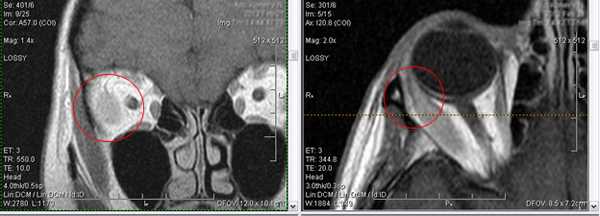

2. Синдром Толоза-Ханта (болезненная офтальмоплегия, синдром верхней глазничной щели)

Характеризуется вовлечением в процесс всех структур, проходящих через верхнюю глазничную щель (артерия, вена, отводящий нерв, блоковый нерв и глазодвигательный нерв, первая ветвь тройничного нерва), и прилегающего к ней кавернозного синуса. Субъективные проявления cиндрома Толоза-Ханта: болезненность в области орбиты, двоение в глазах, экзофтальм и хемоз.

Тот же пациент, исследование в динамике через 4,5 года

Исследование в 2008 году Исследование в 2013 году